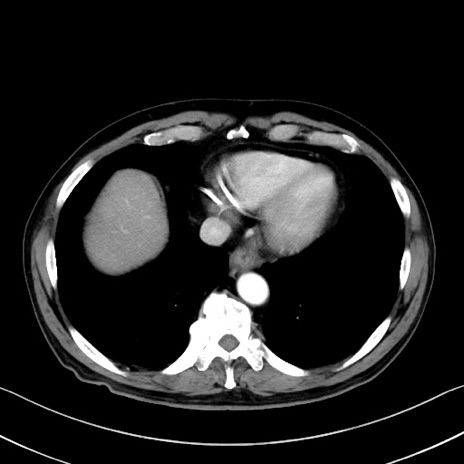

冠状断像

症例35(横断像)

【症例】70歳代 男性

【主訴】腹部膨満、嘔吐

【現病歴】昨日より腹部膨満感出現。本日増悪し、仙痛出現。嘔吐あり、受診。

【既往歴】糖尿病、胆摘後

【身体所見】BP 149/80mmHg、HR 74/min、BT 35.9℃、腹部:膨満、軟、圧痛なし。腸雑音減弱あり。上腹部正中切開瘢痕あり。

【データ】WBC 13500、CRP 1.72